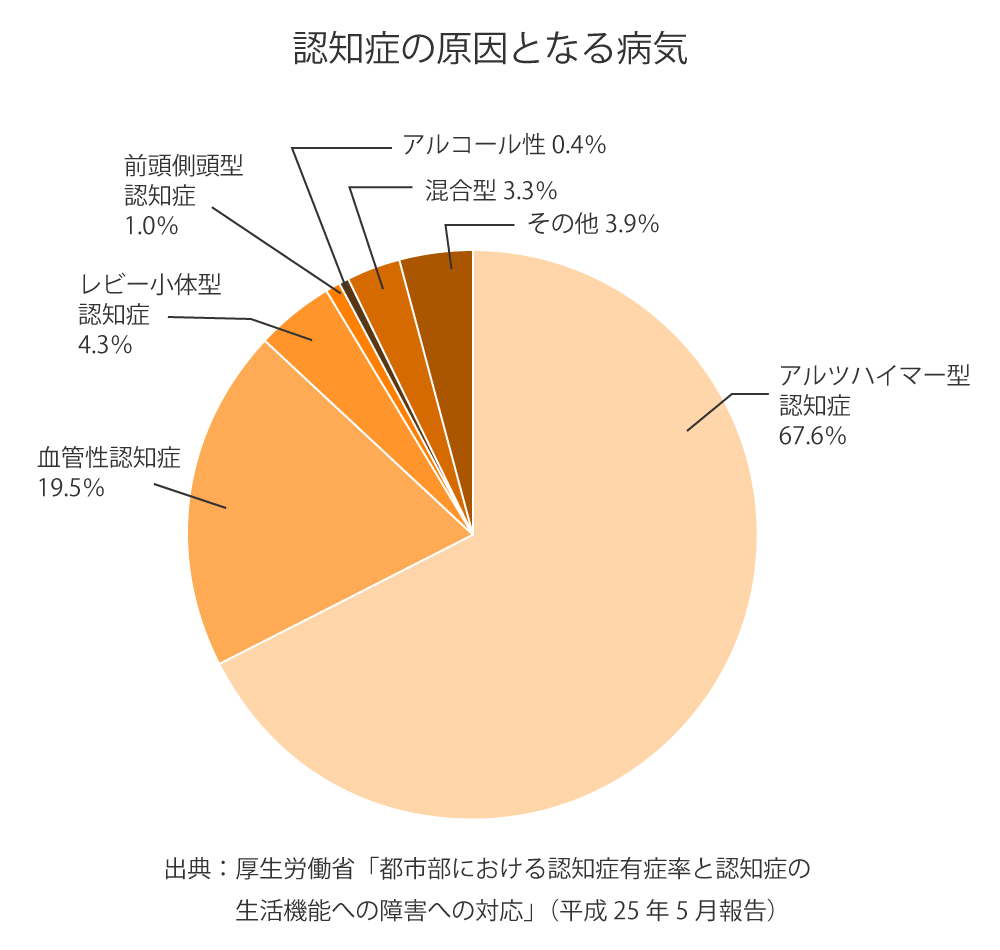

■ 認知症を引き起こす“原因疾患”はいくつもある

認知症は一つの病気ではなく、

その原因となる病気にはいろいろなものがあります。

代表的なものは次のとおりです。

● アルツハイマー病

最も多いタイプで、全体の約6割前後を占めます。

脳にアミロイドβやタウたんぱく質が蓄積し、神経細胞が徐々に減少していきます。

● 血管性認知症

脳梗塞や脳出血の後遺症として起こるタイプ。

脳血管のトラブルによって神経細胞がダメージを受けます。

● レビー小体型認知症

注意力の波・幻視・姿勢の不安定さなどが特徴。

パーキンソン病に似た症状を併発することがあります。

● 前頭側頭型認知症(FTD)

比較的若い年代でも起こり、性格変化や行動の変化が早期から目立ちます。

● その他(正常圧水頭症、慢性硬膜下血腫、甲状腺機能低下症など)

治療が可能な認知症の原因も含まれます。

このように、認知症には複数の原因があり、それぞれ症状の出方も進行の速さも違います。

「認知症」とひとまとめにされるものの、実際には性質の異なる多くの疾患の集合体といえます。